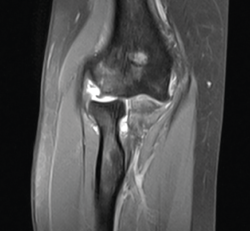

Figura 5. Imagen coronal de resonancia magnética del codo izquierdo, realizada a las 3 semanas de la lesión. Observamos la avulsión proximal del ligamento colateral lateral, la subluxación de la cabeza radial y el edema óseo.